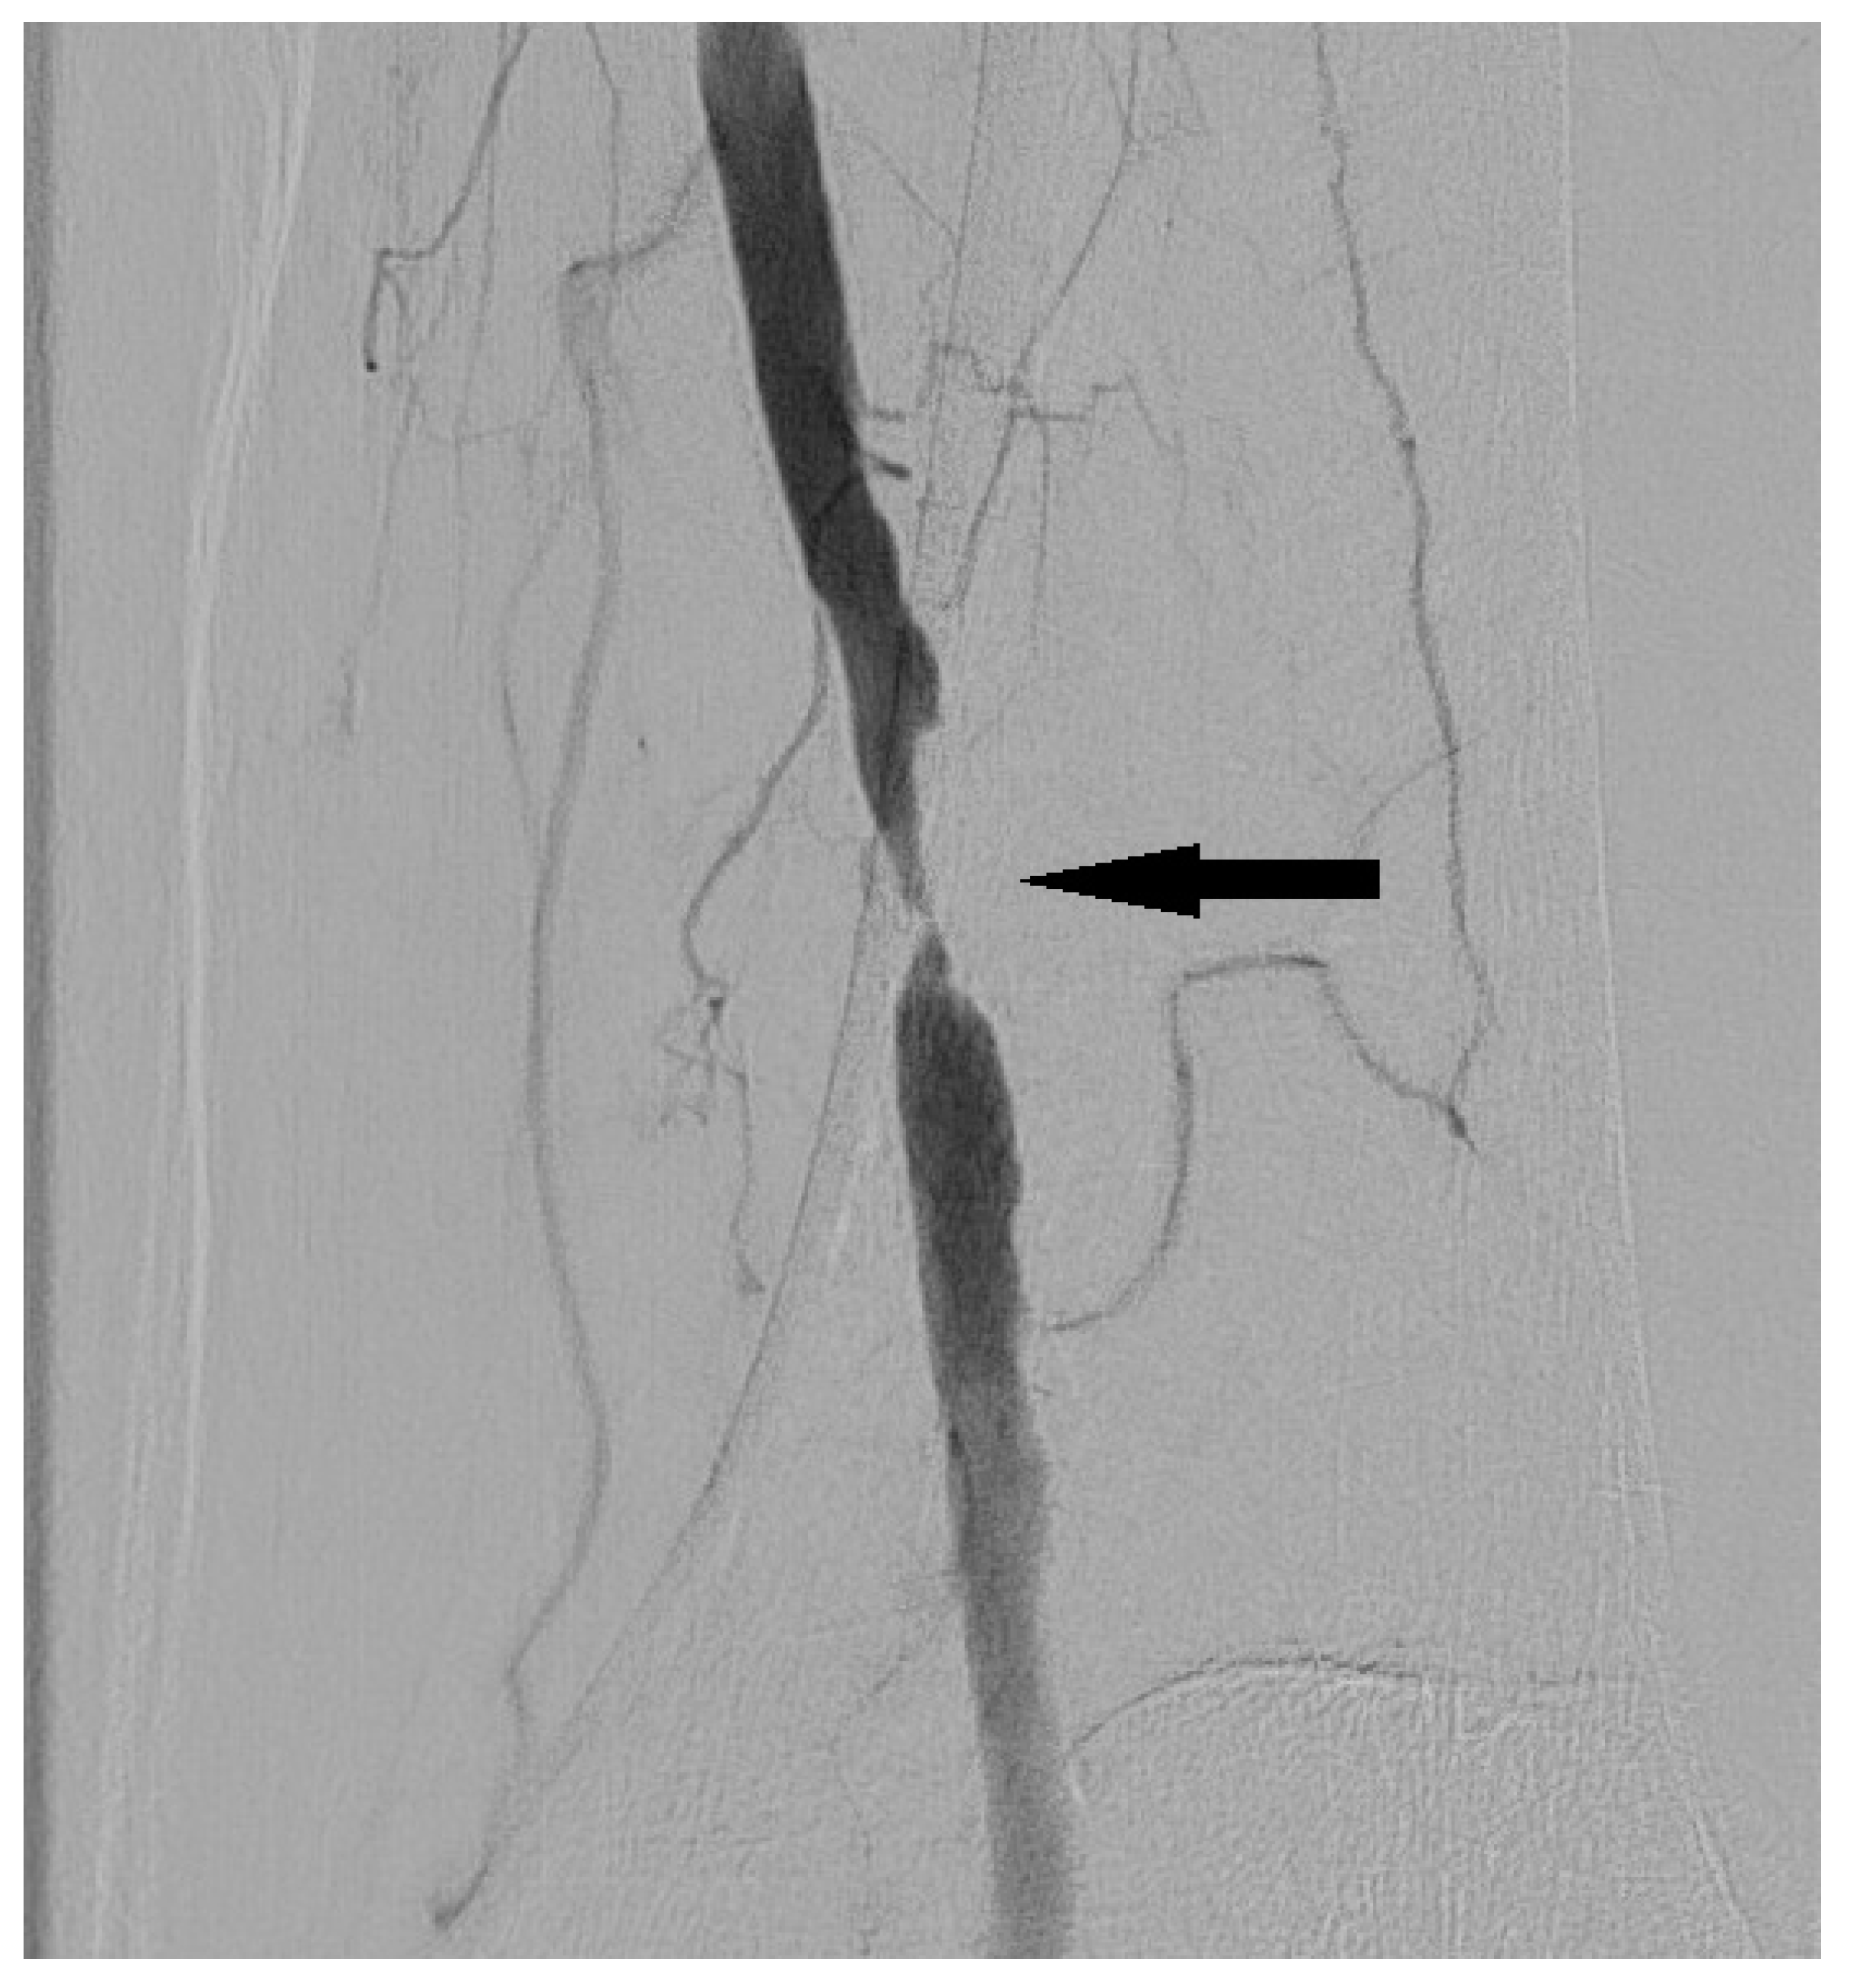

3.2. Dissection